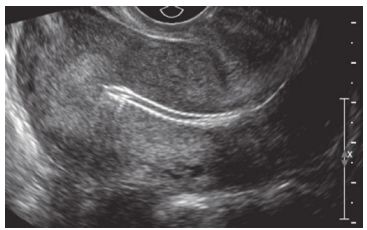

78. 45歲女性,因下腹痛、陰道分泌物多且有異味,到急診求診。照會婦產科,施行陰道 超音波如下圖,下列何者為最有可能之診斷? (A) 內膜鈣化 (B) 避孕器導致之骨盆腔發炎 (C) 子宮內膜增生 (D) 懷孕